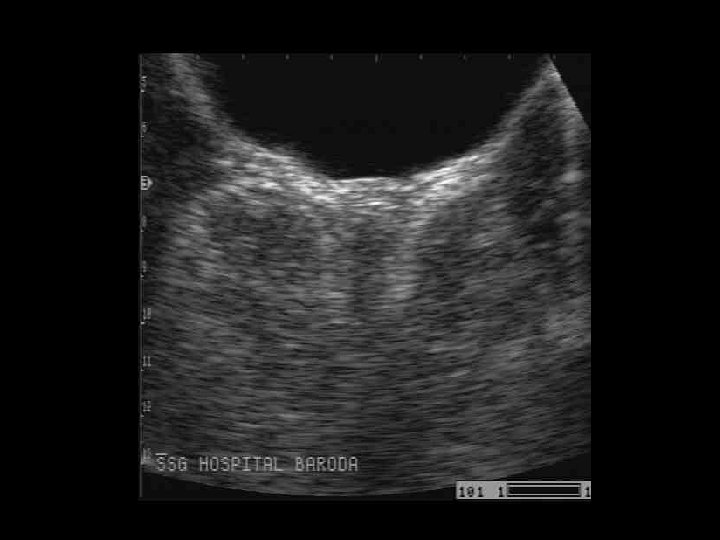

CASE 3

• A 5 yr old girl presented with a h/o lethargy & cough since 4 mth. • On examination pt was anaemic and PEM gr 3. • Has a raised ESR.

The Dense Metaphyseal Band Sign • Dense metaphyseal bands, less commonly known as dense metaphyseal lines, transverse bands, or "lead lines, " indicate radiopaque bone (thicker than the adjacent diaphyseal cortex) at the metaphysis of growing bone, particularly at the wrists and knees.

• 1) 2) 3) 4) 5) In order of decreasing frequency, the causes of a dense metaphysis include Normal variance ( most common cause) Plumbism, Treated leukemia, Healing rickets, Other heavy metal (arsenic, bismuth, mercury) poisoning, 6) Recovery from scurvy, vitamin D hypervitaminosis, 7) Congenital hypothyroidism, hypoparathyroidism, and 8) Transplacental infections (eg, toxoplasmosis, rubella, cytomegalovirus, and herpes).

• Lead poisoning in infants and children may be diagnosed in screening programs, clinically, or radiographically. • Plumbism in children can be traced to pica (eg, dirt eating), acute ingestion of lead-based paints, consumption of home remedies, inhalation of toxic fumes, and rarely, absorption of lead-containing material from metallic or bullet fragments in a serous cavity or joint. • In general, lead lines indicate past lead exposure and correlate with a blood lead level of 50 µg/d. L. • The presence of a dense metaphyseal band at the proximal fibula is a strong indication of plumbism, although the mechanism related to the lead toxicity remains unknown.